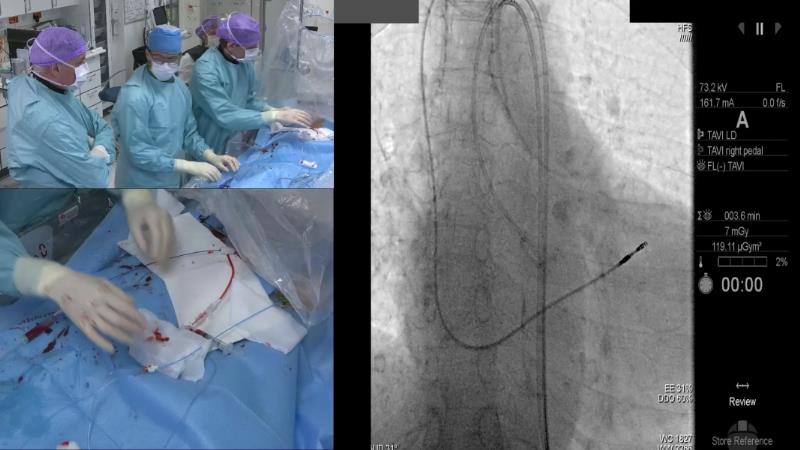

Contemporary best clinical practice for TAVI

This interactive session is designed to show how a good pre-procedural assessment can facilitate the planning of a procedure. It also shows how a certain valve can be best suited for patients with certain phenotypes, and finally how to fully optimise the procedure to obtain the best long term treatment outcome for the patient.